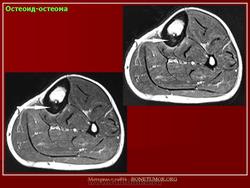

Остеоид - остеома. Остеобластома.

Рентгенологическая картина остеоид-остеомы весьма характерна. Рентгенологические симптомы возникают значительно позже клинических проявлений опухоли, и первым на рентгенограмме обнаруживают склероз кости. На участке поражения формируется одностороннее или муфтообразное утолщение кости в виде гиперостоза. Позднее в толще гиперостоза формируется основной отличительный признак остеоид-остеомы - ее «гнездо» в виде очага разрежения диаметром до 1 см, внутри которого могут отмечаться мелкие костные включения. Сквозь слой склерозированной ткани «гнездо» опухоли на обычных рентгенограммах не всегда дифференцируется и для ее выявления применяют лучи повышенной жесткости и томографию. Обнаружение «гнезда» необходимо для подтверждения диагноза и проведения направленного оперативного вмешательства.